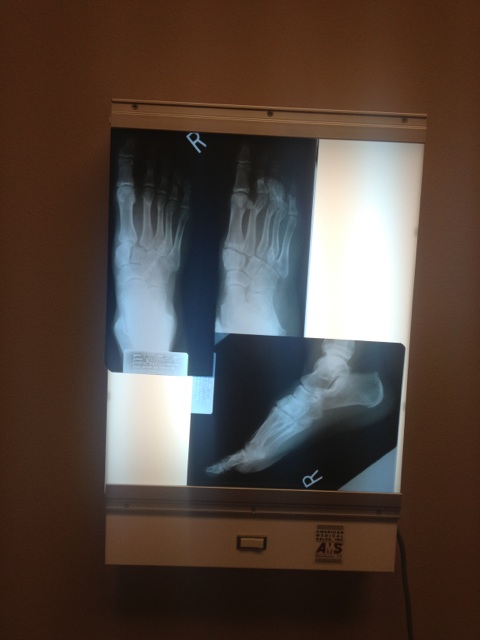

Evan Bourne ha colgado más radiografías tomadas el martes. Él twitteó: «Tenía más radiografías tomadas hoy. Mi índice dedo / pulgar curados en forma de V. Creo que me dará agarre de mono en mis pies como @ ROHDelirious»